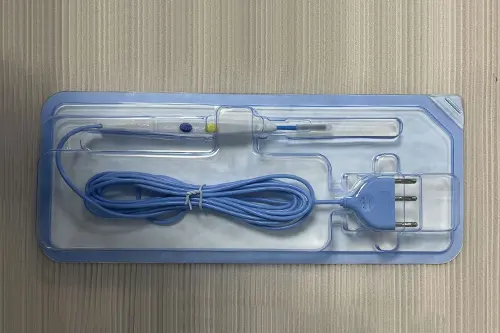

微波消融治疗仪同品种临床评价案例

三类器械注册